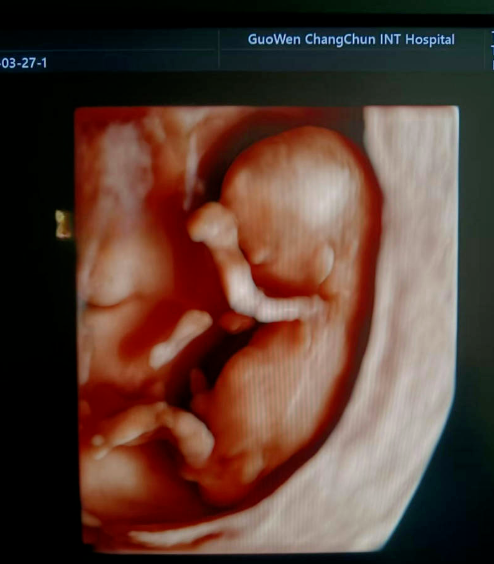

通常在懷孕 11 周 - 13 周 + 6 天之間進(jìn)行。這個(gè)時(shí)期胎兒大小適中,頸項(xiàng)透明層的顯示較為清晰,測量結(jié)果也相對(duì)準(zhǔn)確,能更好地發(fā)揮 NT 檢查對(duì)胎兒異常的篩查作用。

超聲檢查,孕婦無需空腹。檢查時(shí),超聲醫(yī)生會(huì)使用超聲儀器對(duì)胎兒頸部進(jìn)行仔細(xì)觀察和測量。通過超聲探頭可以清晰地看到胎兒在子宮內(nèi)的情況,重點(diǎn)測量胎兒頸項(xiàng)部皮下無回聲透明層最厚的部位,測量值即為 NT 值。正常胎兒 NT 值一般不超過 2.5mm。